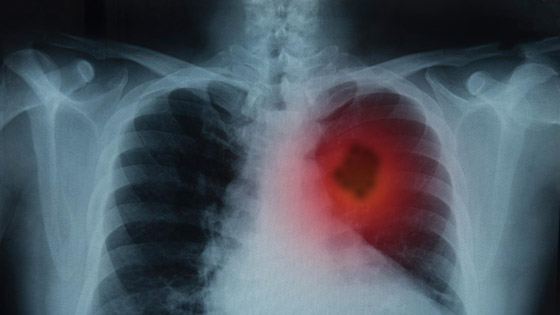

يؤكد العلماء وخبراء التغذية أن هناك أكلات وأنظمة غذائية من شأنها تعزيز صحة الجهاز التنفسي والحفاظ على صحة الرئتين. ونشرت صحيفة عالمية أن هناك عدة أطعمة ومشروبات غنية بالمعادن والفيتامينات ومضادات الأكسدة لها تاثير كبير في تعزيز صحة الرئتين والجهاز التنفسي بشكل عام ومنها: